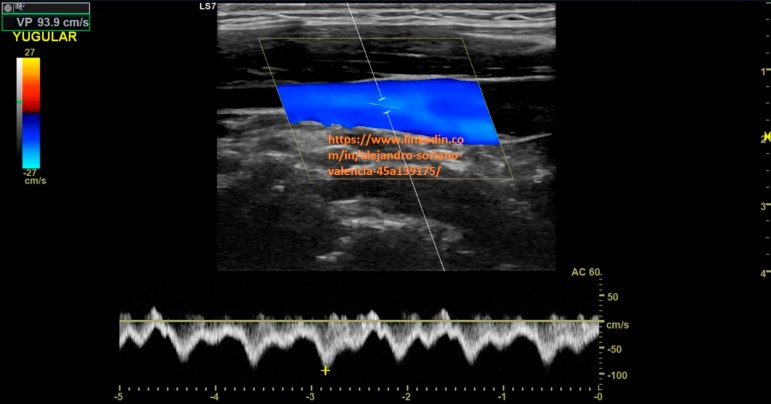

2. Yugular interna longitudinal. Estudio triplex.

Como vimos en el post nº 105 las venas tienen un patrón monofásico. Pues

bien, aquí tenemos dos excepciones, y es que, nos encontraremos con un

flujo pulsátil en las venas yugular interna y subclavia.

will become infraclavicular. It is a vessel with very difficult access, so we are not able to make transversal cuts and we will not be able to compress properly. As we saw in post no. 105, the veins have a monophasic pattern. Well, here we have two exceptions, and that is that, we will find a pulsating flow in the internal jugular and subclavian veins.